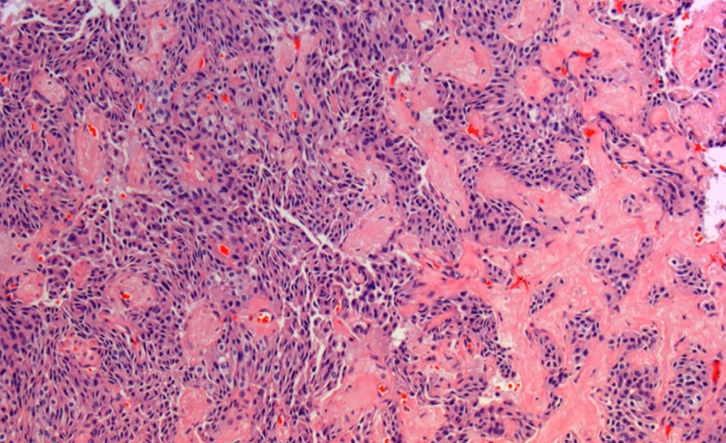

-nodular hyperplasia

-disruption of follicular architecture

follicular adenomatoid hyperplasia, follicular adenoma, MIFTC, angioinvasive FTC

-follicular adenomatoid hyperplasia

-not a distinct/discreet lesion